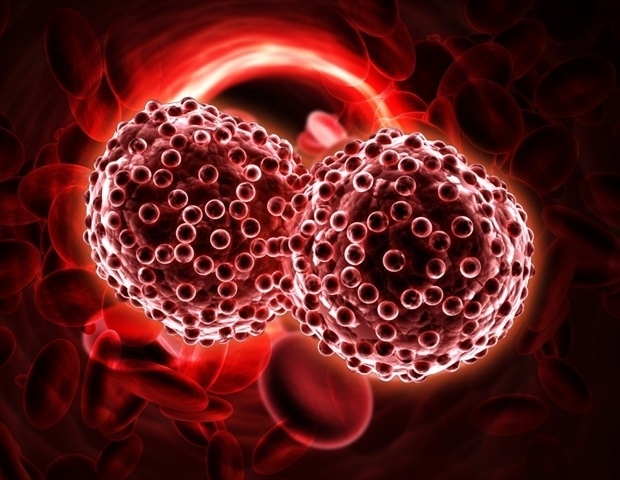

מדענים מאוניברסיטת טקסס באל פאסו מצאו יעד חדש ומבטיח במאבק נגד קרצינומה סרוסית בדרגה גבוהה, צורה אגרסיבית של סרטן השחלות.

מדענים מאוניברסיטת טקסס באל פאסו מצאו יעד חדש ומבטיח במאבק נגד קרצינומה סרוסית בדרגה גבוהה, צורה אגרסיבית של סרטן השחלות.

הסרטן נותר אחד האתגרים הקריטיים ביותר בבריאות הציבור העולמית, המפעיל עומסים חברתיים, כלכליים וקליניים עמוקים תוך הגבלת רווחים בתוחלת החיים